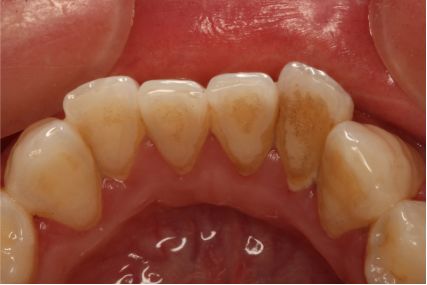

女,38岁,主诉牙龈出血1年,无系统疾病及药物过敏史。检查:牙列式18-27、37-47;18伸长,无咬合;口腔卫生欠佳,可见牙石、软垢,后牙区牙石软垢较多,全口牙龈边缘充血水肿,探诊出血阳性,牙周探诊深度3-4mm。诊断为慢性牙周炎(轻度)。

术前